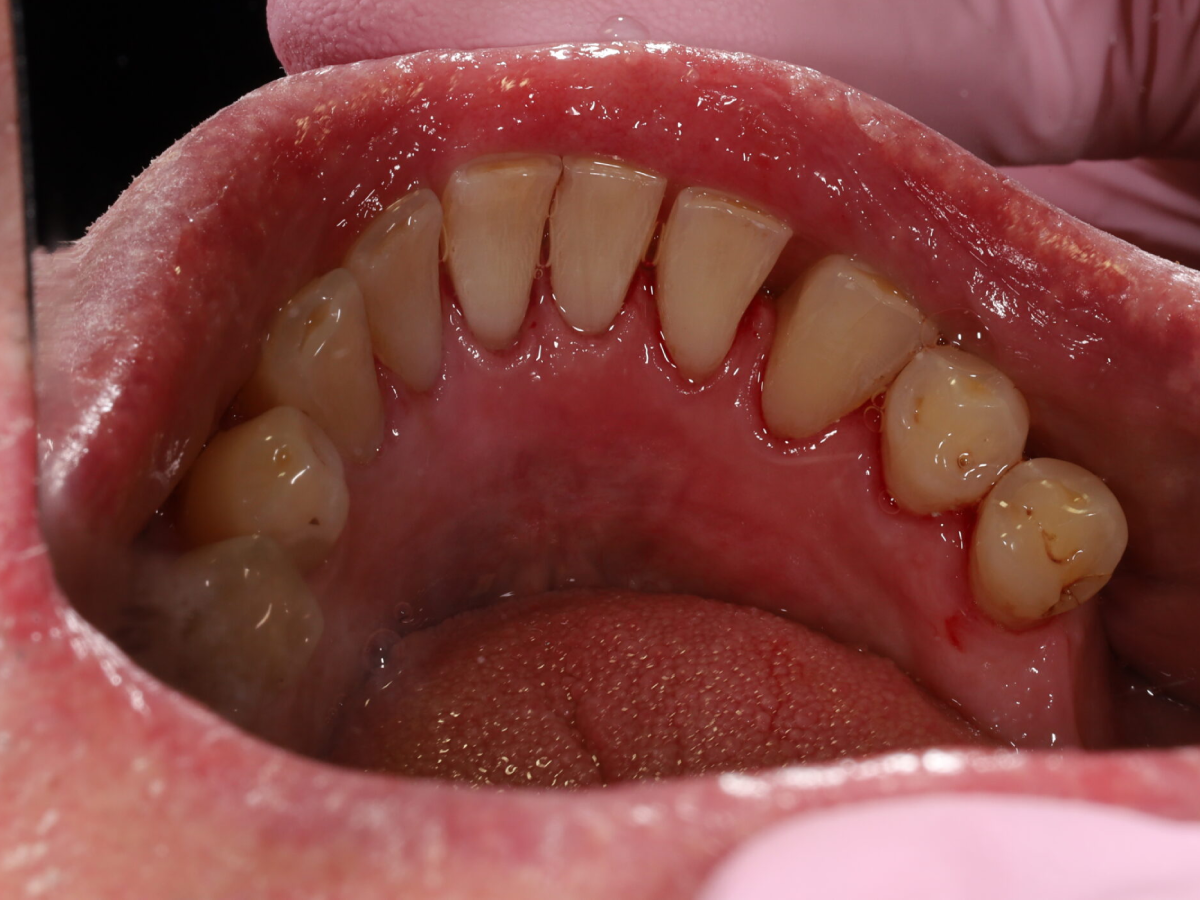

Pełna higienizacja: usunięcie kamienia i osadu (scaling, piaskowanie).

Profesjonalne czyszczenie zębów: scaling, polerowanie i fluoryzacja.

Metamorfoza uśmiechu: usunięcie przebarwień i kamienia nazębnego.